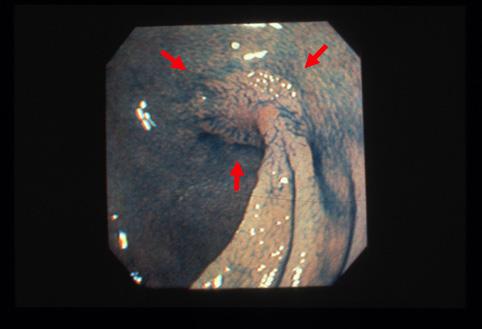

얕은 함몰형의 변연에 잠식상을 나타내고、점막의 도상유잔(인젤)을 동반한 표면함몰형(IIc형)의 조기대장암(IIc형)의 조기대장암

0형(표재형)/IIc형(IIc)

15~19

m